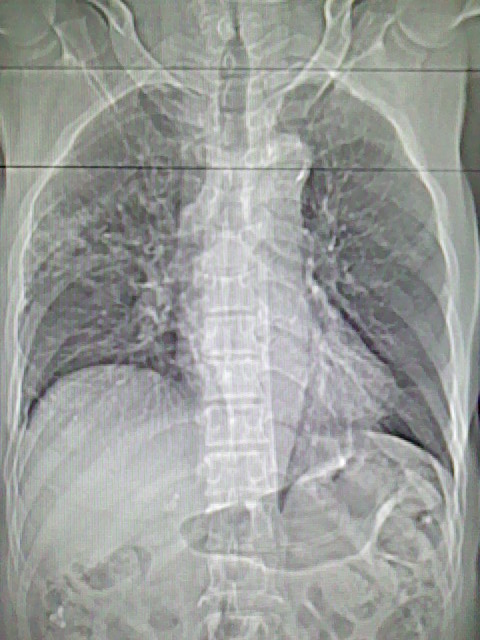

男,70岁,脑出血,长期卧床,左侧背部可触及肿块

右肺病灶考虑炎症性。

慢性间质性炎症,与老年患者长期卧床相关,胸壁软组织及肋骨未见异常。

右肺病灶考虑炎症性

考虑右肺及左肺下叶炎症。

右肺及左肺下叶炎症。

考虑右肺及左肺下叶慢性炎症。

肺部感染,背部筋膜增厚,考虑坠积性水肿或炎症

右侧肺部见片状密度增高影,边缘模糊。考虑炎症。另食管壁增厚。

右肺肺气肿并炎症。

右肺上叶前段病呈楔形,其尖端指向肺门,考虑肺动脉栓塞可能性大.